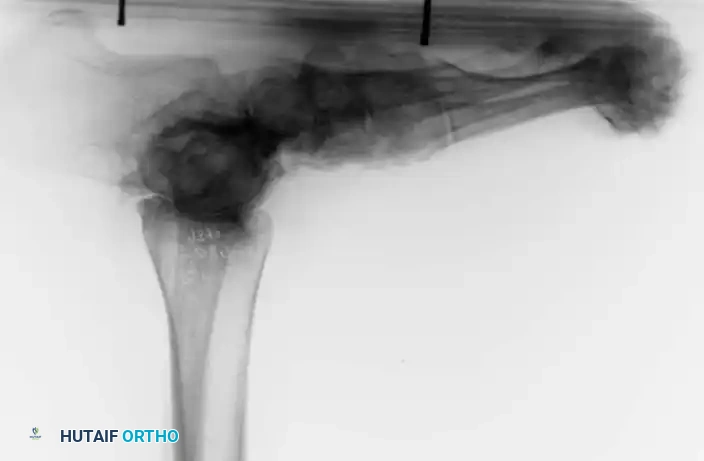

Fig. 81-6 (A) Heel valgus and foot pronation secondary to RA. If the subtalar and midtarsal joints are surgically reduced, the forefoot may be in pronounced supination relative to the hindfoot, complicating first ray plantarflexion. (B) Radiographic evidence of multiple severe dislocations of the MTP joints.

Fig. 81-9 (A, B) Radiographic evidence of bony proliferation at the distal end of the resected metatarsals. This remodeling can lead to recurrent plantar pressure and necessitates adequate initial resection.

Common long-term objective recurrences include:

1. Recurrence of hallux valgus (if arthrodesis was not performed or failed).

2. Dorsal posturing of the lesser phalanges on the metatarsal remnants.

3. Bony proliferation (osteophyte formation) on the distal ends of the resected metatarsals, leading to recurrent plantar keratoses.